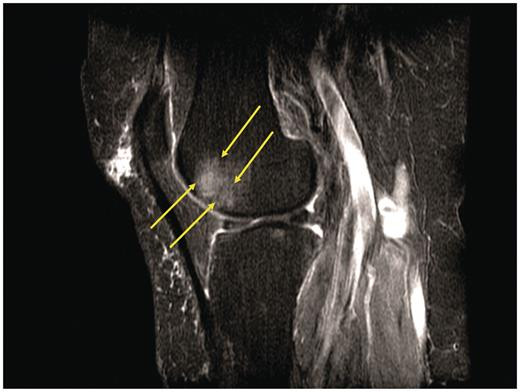

【前十字韌帶】韌帶斷裂怎麼辦?

受傷時感覺或聽到膝蓋有啪的聲音。

淺談十字韌帶(Cruciate Ligament)

大家知道掌握膝關節移動及旋轉的穩定樞紐是什麼嗎?答案就是十字韌帶!

「十字韌帶斷裂」,是否該進行手術?

關於「十字韌帶斷裂」,雖並非每個個案都需立即進行手術,經由專業醫師的判斷才可給予最適當的治療計畫!